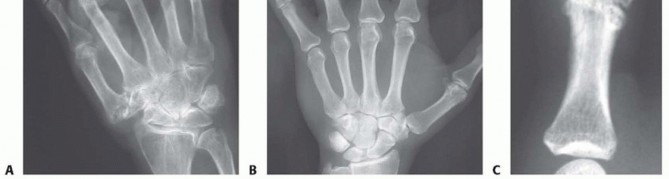

Radiographic evaluation begins with high-quality, orthogonal plain films (Anteroposterior, Lateral, and true Oblique views). These images are scrutinized for joint space narrowing, periarticular erosions, osteophyte formation, and the degree of subluxation.

FIG 1 • A. Rheumatoid arthritis affecting hand, with most notable disease affecting metacarpophalangeal (MCP) joints. The wrist is also affected.

FIG 1 • B. Isolated osteoarthritis of the MCP joint of the long finger.

Digital templating is a critical step. Using standardized radiographic markers, the surgeon templates the medullary canals of the metacarpals and phalanges to estimate the required implant sizes. The goal is to select an implant stem that fills the canal without causing excessive cortical tension, which could lead to intraoperative fracture. The hinge of the implant must sit flush against the resected bone surfaces without being compressed. It is imperative to ensure that a full array of implant sizes, including half-sizes, is available in the operating room, as radiographic templating is an estimate that must be confirmed with intraoperative broaching and trialing.